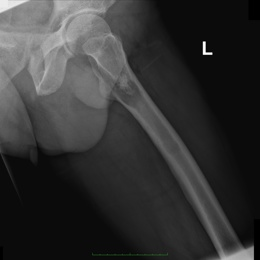

Radiographic imaging is used to help form a diagnosis. These include X-Ray, MRI, CT and Bone Scans.

An example of a dedifferentiated chondrosarcoma X-Ray is shown.